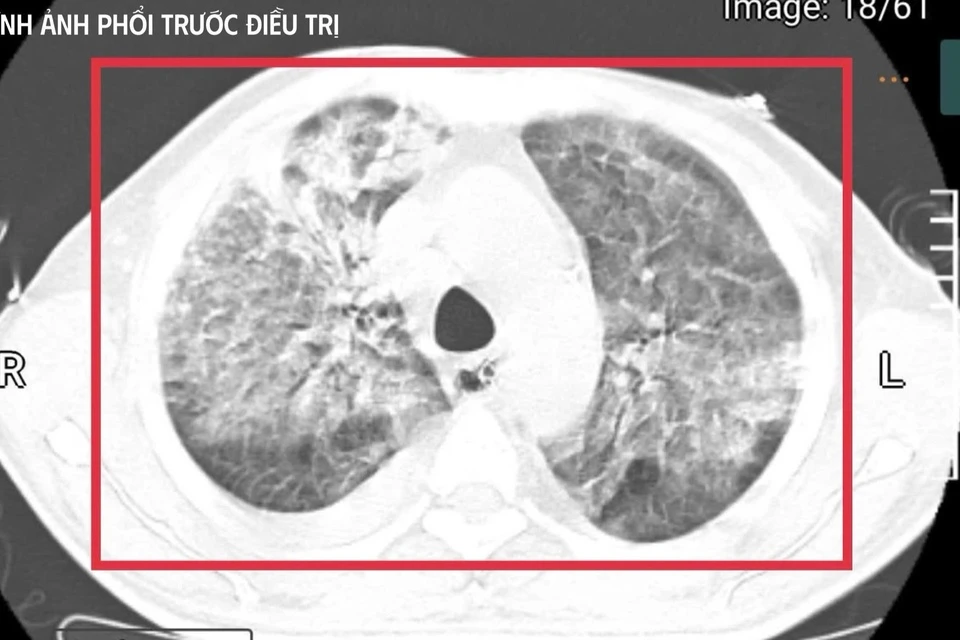

Bệnh nhân 35 tuổi từ vùng lưu hành vi khuẩn mang bệnh Whitmore trở về trong tình trạng nguy kịch, sốc nhiễm khuẩn, suy đa tạng, thân nhiệt hơn 41°C và hôn mê sâu.

Bệnh nhân nam L.V.T. (35 tuổi, quê Nghệ An) sinh sống và làm việc tại Thái Lan - khu vực lưu hành bệnh Whitmore cao. Anh có tiền sử đái tháo đường mới phát hiện. Khoảng 5 tuần trước khi về Việt Nam, người đàn ông xuất hiện sốt cao liên tục, khó thở, kích thích nhiều, phải nhập cấp cứu tại một cơ sở y tế ở Thái Lan.

Tại đây, bệnh nhân được đặt nội khí quản thở máy; kết quả cấy máu xác định nhiễm Burkholderia pseudomallei - tác nhân gây bệnh Whitmore. Dù được điều trị ban đầu, tình trạng vẫn diễn tiến nặng nên gia đình xin chuyển về Việt Nam để tiếp tục điều trị. Nhưng chỉ sau ít ngày, người đàn ông này rơi vào sốc nhiễm khuẩn, suy đa tạng, sốt cao liên tục, rối loạn ý thức và được chuyển gấp ra khoa Cấp cứu, Bệnh viện Bệnh Nhiệt đới Trung ương (Hà Nội).

Thạc sĩ, bác sĩ nội trú Nguyễn Kim Anh, khoa Cấp cứu, cho biết thời điểm tiếp nhận người bệnh là "khoảnh khắc rất căng thẳng". Bệnh nhân hôn mê sâu, thang điểm Glasgow chỉ còn 9, mất phản xạ đường thở, phụ thuộc hoàn toàn vào máy thở. Nhiệt độ liên tục 41-42°C kèm run cơ toàn thân, gợi ý tình trạng tăng thân nhiệt ác tính trên nền nhiễm khuẩn huyết tối cấp.

Xét nghiệm cho thấy men gan và bilirubin của anh T. tăng cao, rối loạn đông máu, creatinin tăng nhanh kèm vô niệu - biểu hiện của suy gan, suy thận cấp tiến triển. Nồng độ CK vượt quá 100.000 U/l, kèm đau cơ và nước tiểu sẫm màu, phù hợp với tiêu cơ vân cấp.

Không chỉ vậy, các chỉ số viêm như CRP, PCT tăng rất cao, phản ánh tình trạng nhiễm trùng, nhiễm độc toàn thân dữ dội. Trên nền đó là đái tháo đường chưa kiểm soát và viêm gan C mạn, khiến cơ thể người bệnh càng suy sụp.

Người bệnh rơi vào sốc nhiễm khuẩn, suy đa tạng, sốt cao liên tục, rối loạn ý thức và được chuyển gấp ra khoa Cấp cứu, Bệnh viện Bệnh Nhiệt đới Trung ương (Hà Nội). Ảnh: BVCC

Theo bác sĩ Kim Anh, đây là một trong những thể tối cấp của Whitmore, nhiễm khuẩn huyết nặng, suy đa tạng, rối loạn chuyển hoá sâu và nguy cơ không qua khỏi rất lớn trong thời gian rất ngắn nếu không được hồi sức tích cực ngay lập tức.

Đội ngũ bác sĩ đã phải "chạy song song" nhiều can thiệp: an thần sâu để kiểm soát kích thích và bảo vệ não, hạ thân nhiệt chủ động nhằm khống chế tình trạng tăng thân nhiệt ác tính, thiết lập đường truyền trung tâm, theo dõi huyết động liên tục, điều chỉnh toan - điện giải, phối hợp kháng sinh theo phác đồ điều trị Melioidosis và tiến hành lọc máu liên tục nhiều ngày để hỗ trợ chức năng thận, loại bỏ độc chất và giảm gánh nặng viêm.

Sau khoảng 3 ngày hồi sức cao độ, bệnh nhân bắt đầu cắt sốt, các chỉ số viêm giảm dần, huyết áp ổn định hơn với nhu cầu vận mạch giảm, chức năng gan thận cải thiện, tri giác dần hồi phục. Người bệnh cai được thở máy qua mở khí quản, tập lại hô hấp tự nhiên và phục hồi vận động.

Trong 3 tuần điều trị tích cực tại khoa Cấp cứu, các bác sĩ tiếp tục tối ưu kháng sinh, kiểm soát chặt chẽ đường huyết, hỗ trợ dinh dưỡng và phục hồi chức năng sớm. Người bệnh hồi phục từng bước, tỉnh táo hoàn toàn, tự thở khí phòng với SpO₂ 99%, huyết áp 130/80 mmHg, cơ lực chi trên đạt 5/5, chi dưới 4/5, đủ điều kiện ra viện và tiếp tục theo dõi ngoại trú.